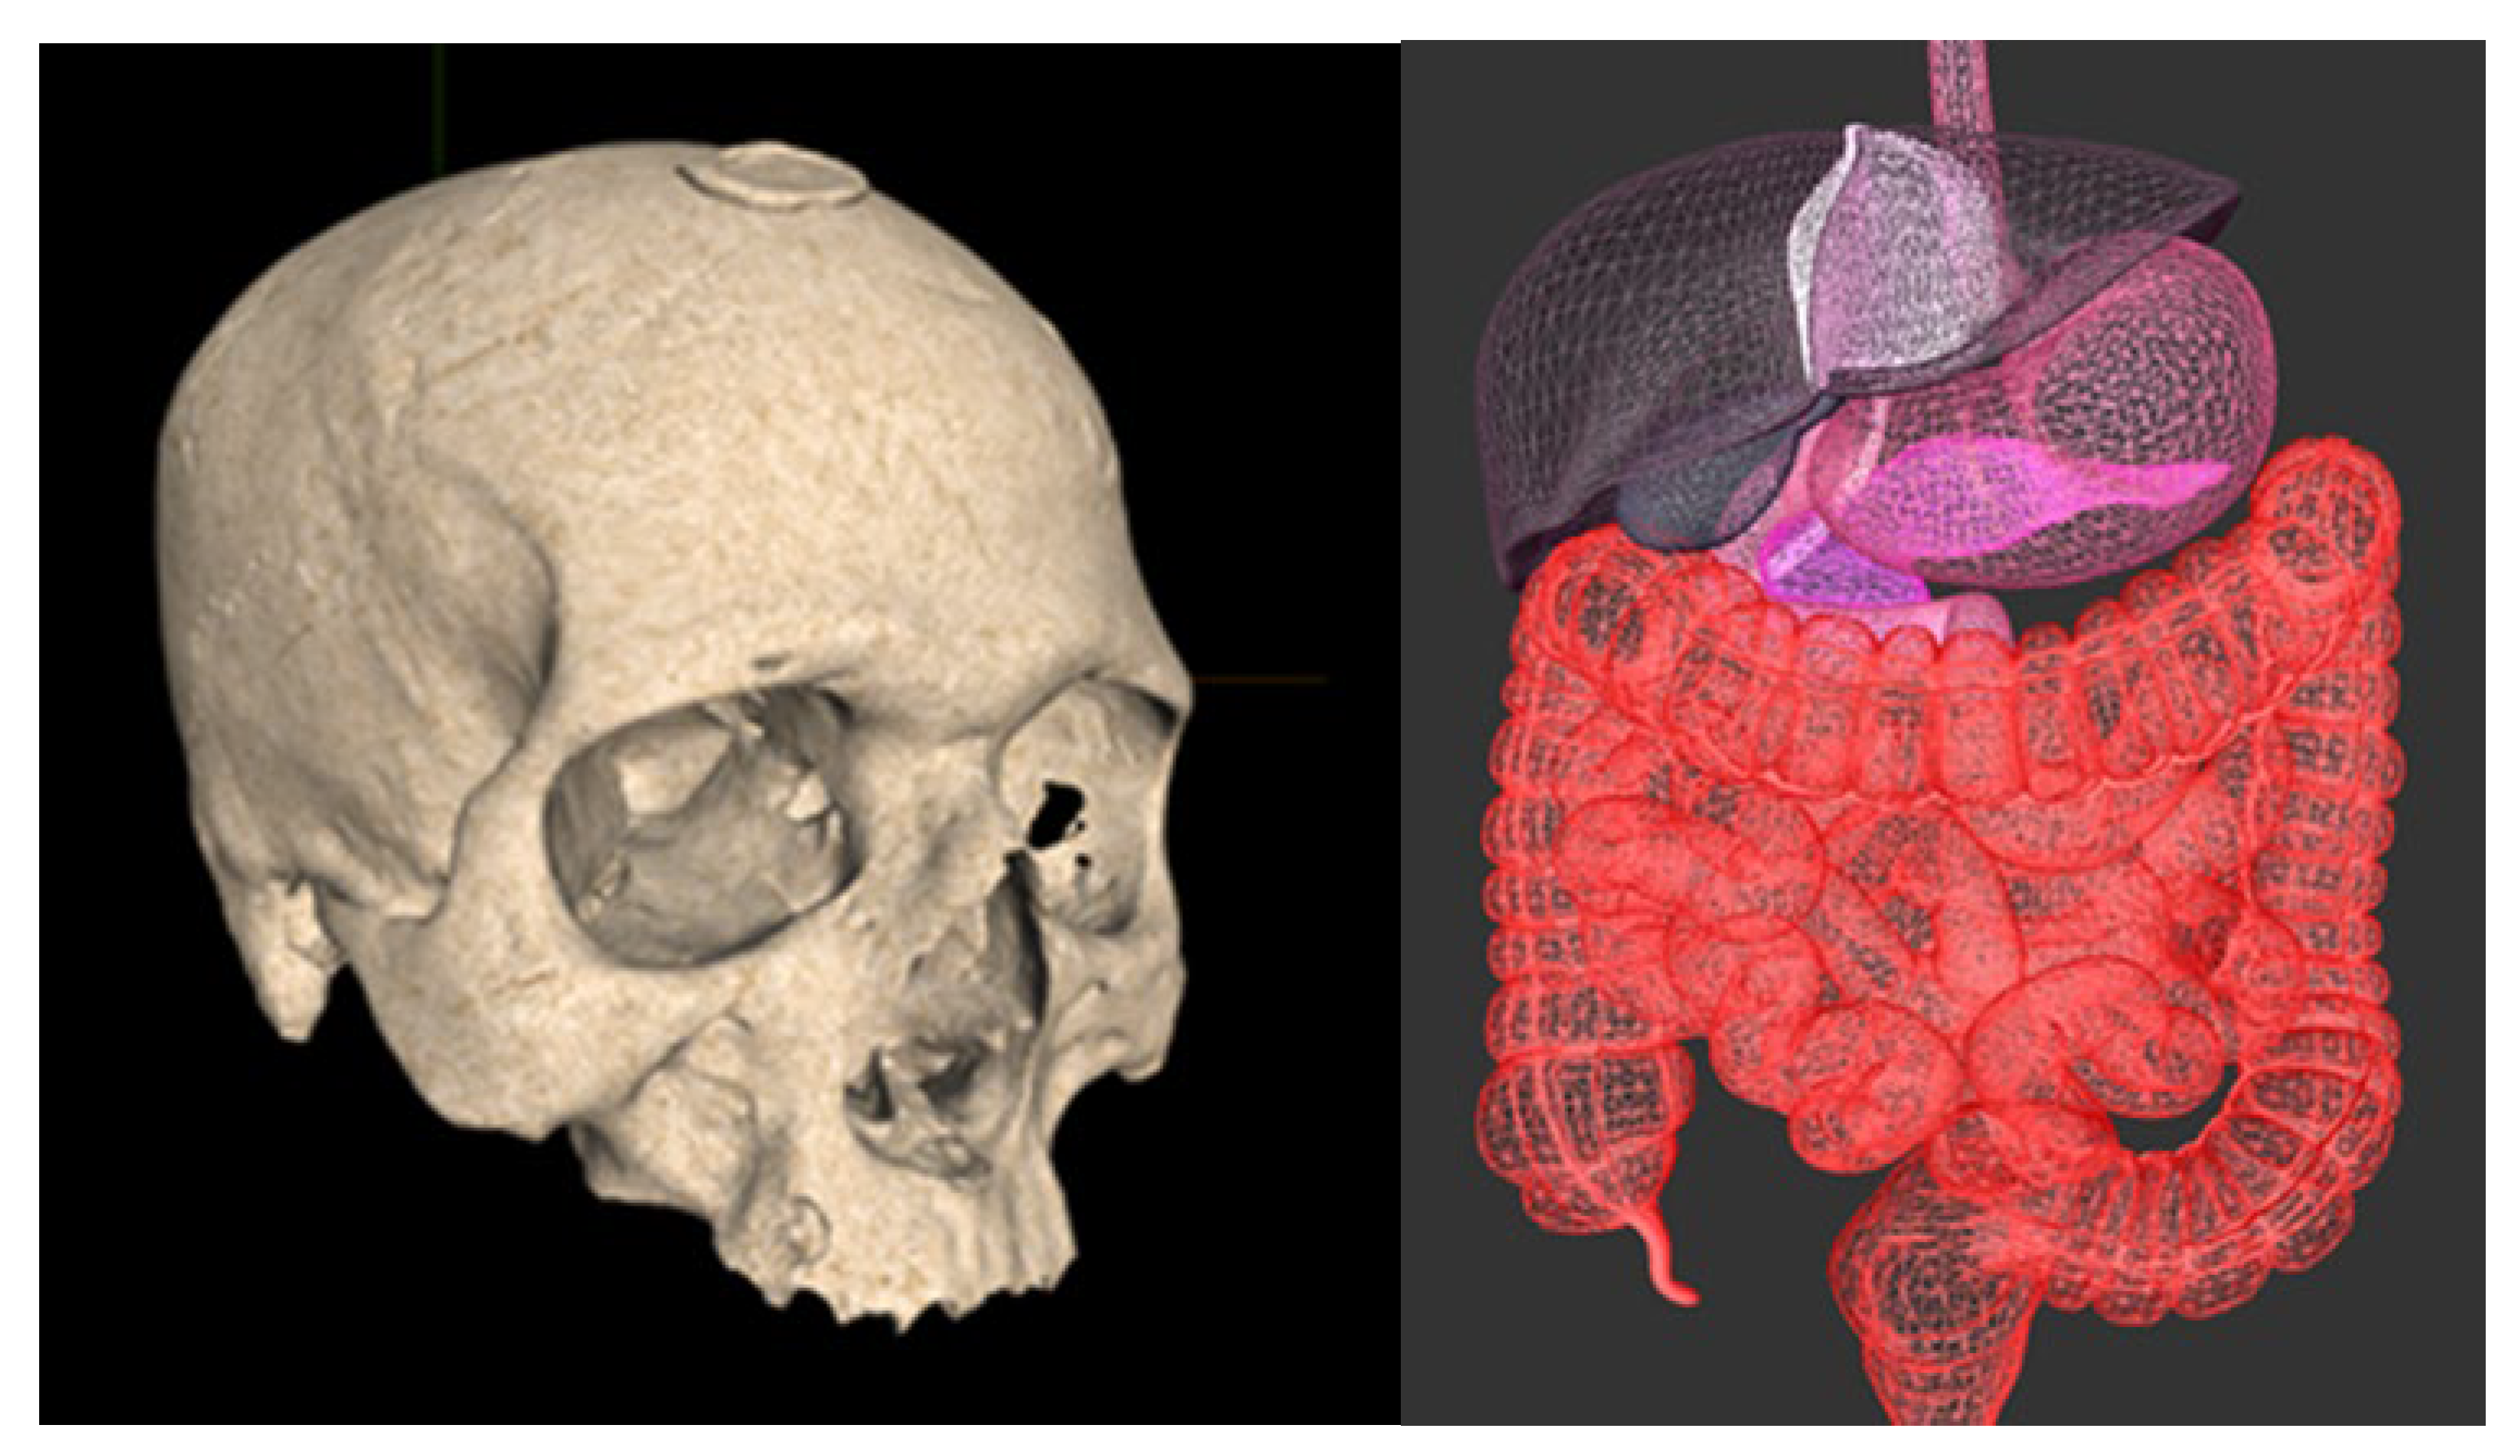

With reference to Figure 13, we show a human skull of a catholic saint that is rendered in the solid mode and a human abdomen. The skull model represents a skull (cranium) of a catholic relict—it is created by a professional 3D scanner and is a part of the Interactive Virtual Shrine (IVS) project [43], which provides anthropological and religious aspects of catholic relicts. Its vertex attributes are position, normal, and texture coordinates, and it is rendered in the solid mode. The abdomen model is created by a DCC tool; its vertex attributes are position, normal, and color; and it is rendered in the wire-frame mode without culling back triangles.

Many techniques including deep and machine learning [44] have been developed for the segmentation [45], reconstruction [46], and registration [47] of images, including medical ones. VanityX supports various volume rendering techniques such as texture-based rendering, ray-cast rendering, and rendering using transfer functions. With reference to Figure 15, we render a slice of a human abdomen (liver) and a human skull. The slice of a human abdomen is anonymized and rendered using texture-based rendering, where each axial slice is represented as a texture mapped (sampled) onto a quad. The human skull is rendered using transfer functions that map scalar data onto color and opacity to depict relevant features of the model being rendered.

Figure 13. Rendering triangle meshes with VanityX. The relict on the left side is stamped with the papal seal. It is provided by courtesy of Reverend Marijan Jelenić, the catholic church in Vodnjan, Croatia. On the right, we render a human abdomen.

Figure 15. Volume rendering via textures and transfer functions. On the left is a model provided courtesy of Dragan Schwarz from hospital Radiochirurgia, Croatia, while the second model is a free one.